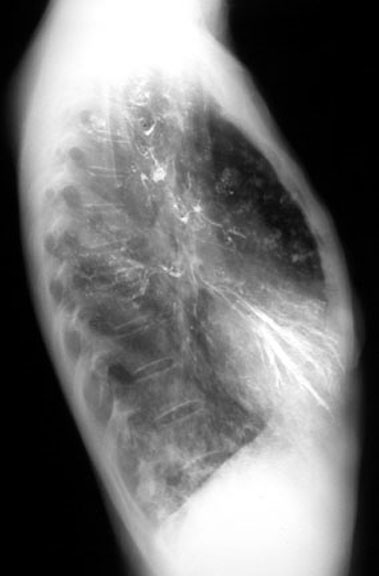

• Dye in bronchi following esophogram